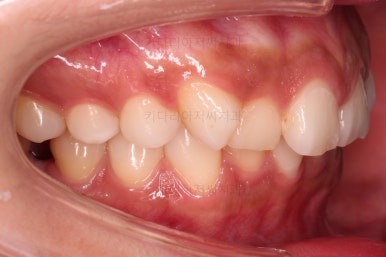

가지런한 느낌 좋고요.

교합도 잘 맞고 이 뽑은 자리도 틈이 없으며 사랑니 당겨온 자리도 틈새 없이 잘 마무리가 되었네요.

연산동교정치과 전후 비교해 보겠습니다.

얼굴모습도 약간 나와있던 윗입술 느낌도 완벽히 개선되었고요.

전반적으로 깔끔하게 임플란트 없이 결손치아 부분을 잘 마무리 했습니다.